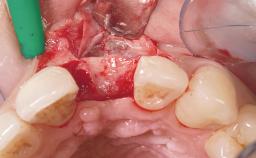

A 30-year-old female patient was referred to the office for the treatment of tooth 11. Her chief concern at the initial visit was to inquire, “Why is my tooth pink?” Upon clinical examination, it was determined that tooth 11 had a previous history of trauma and that the clinical crown had become noticeably pink in color as a result of internal resorption. This diagnosis was confirmed radiographically, indicating a large radiolucency involving the central and distal portions of the clinical crown. It was determined that restoration of this tooth was not possible, and that extraction was indicated. The presence of a mid-line diastema, which the patient wanted to reproduce, directed the treatment plan for tooth replacement utilizing a dental implant.

Bone Augmentation Horizontal|Simultaneous

Augmentation Materials Autogenous chips|Membrane

Placement Protocol Immediate implant placement

Socket Integrity Sufficient, with intact bone walls

Bone Volume Sufficient, with intact walls